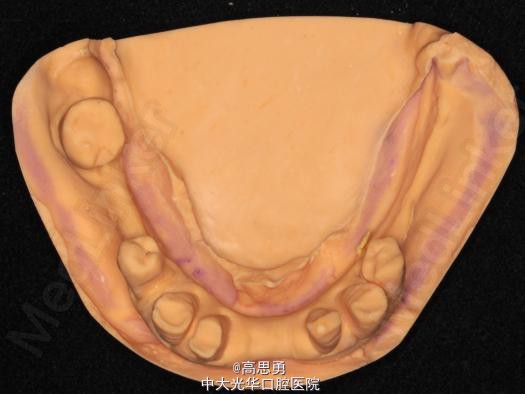

2、研究模型 调拌藻酸盐印模材料于2号成品托盘上取上下颌研究模,灌注石膏模型,研究分析、制定治疗计划,并制作个别托盘。

3、基牙预备 对#13近中、#23远中、#27近中、#34近中、#47近中常规制备支托凹,抛光。

4、工作模型 调拌藻酸盐印模材料于个别托盘上。做一定的边缘整塑,取上下颌研究模,灌注石膏模型。